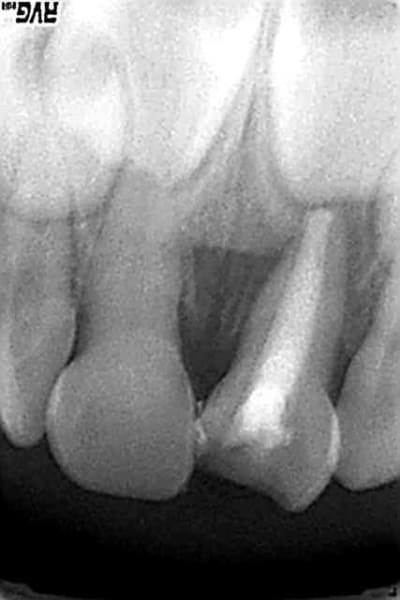

je déterre le post parce que je suis contente de moi:))

4615 1 m6knoz - Eugenol

4615 2 reik2x - Eugenol

4615 3 vwp5f6 - Eugenol